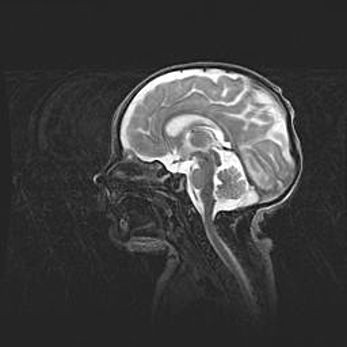

Аномалия Денди-Уокера. Признаки гипоплазии мозолистого тела.

Возраст: 5 месяцев 3 дня

Вес: 5550 г

Пол: мужской

Окружность головы: 39 см

Срок гестации: 40 недель

Аномалия Денди-Уокера – это порок развития головного мозга, для которого характерна триада симптомов: гипотрофия или аплазия червя мозжечка и/или полушарий мозжечка, расширение четвёртого желудочка с формированием ликворной кисты задней черепной ямки, гипертензионная гидроцефалия различной степени.

Гипоплазия мозолистого тела относится к дефектам внутриутробного этапа развития мозговой ткани, возникающим в процессе закладки структур головного мозга, что происходит на начальных этапах развития эмбриона.